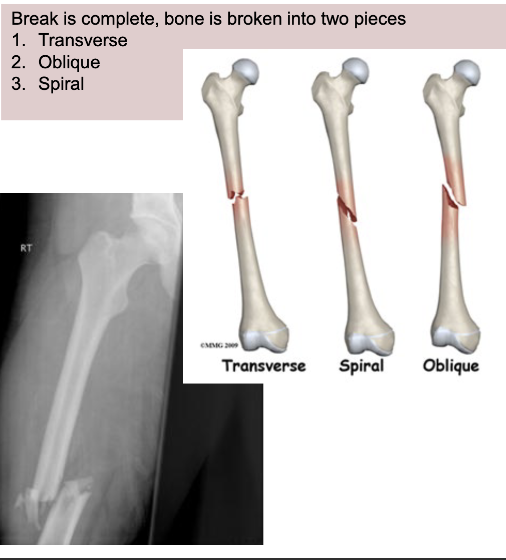

What is a complete fracture?

Break is complete, bone is broken into 2 pieces

Transverse

Oblique

Spiral

What fracture is this?

Oblique - complete

Spiral - complete

Transverse - complete